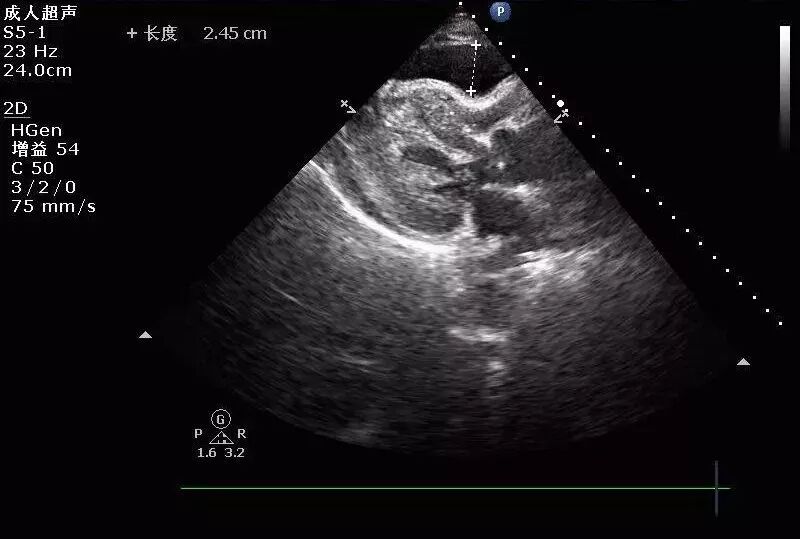

(图5)

图5: 2017年8月30日复查经胸超声心动图提示:左室靠近心尖处血肿形成。少量心包积液。左室靠近心尖处外壁可见一低回声包块,大小约40mmx21mm,边界尚清。